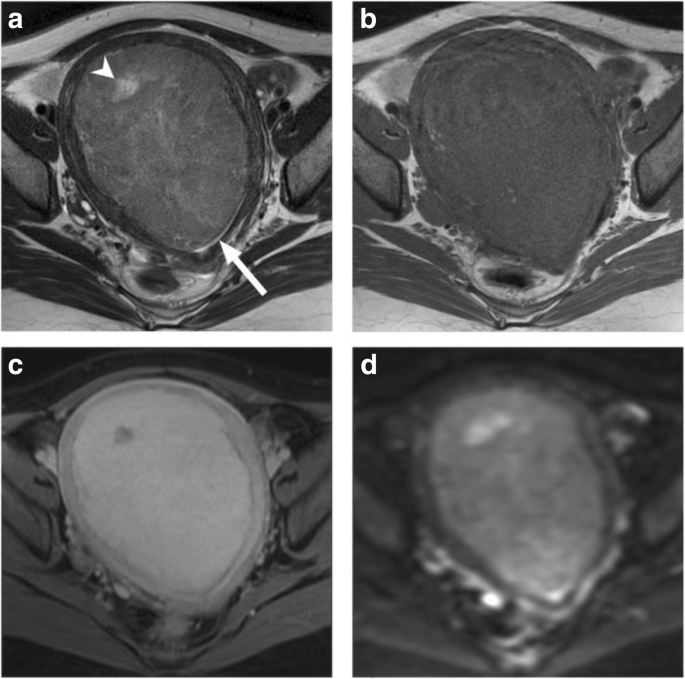

A 61-year-old woman had a 14.5-cm infiltrative tumor involving both endometrial cavity and myometrium. a Axial T2WI image shows hyperintensity within the solid tumor representing necrosis (arrowhead). b Axial T1WI image demonstrates hyperintensity representing hemorrhage (asterisk). c Post-contrast fat-saturated T1WI shows feather-like enhancement (arrow) within the tumor. d H&E stain shows small round cells with mitotic figures, as well as extensive necrosis and intratumoral hemorrhage. Pathology report yielded a high-grade endometrial stromal sarcoma